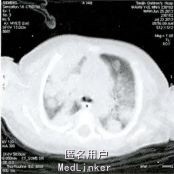

精神反应欠佳,呼吸平顺,无发绀,面部可见散在脓疱疹,前囟平软,双肺可闻及中细湿啰音,心音有力,律齐,腹软不胀,脐周红,可见少许脓性渗出。血常规:WBC 25.4×10^9/L,N 0.677,CRP 48.6mg/L。血培养及尿培养示:曲霉菌感染。肺部CT示双肺可见多发散在团状及结节状高密度影。

诊断为:肺曲霉菌病 予伏立康唑12mg/(kg·d),每日2次,退热、补液等对症处理。患儿病情好转出院,门诊继续治疗。